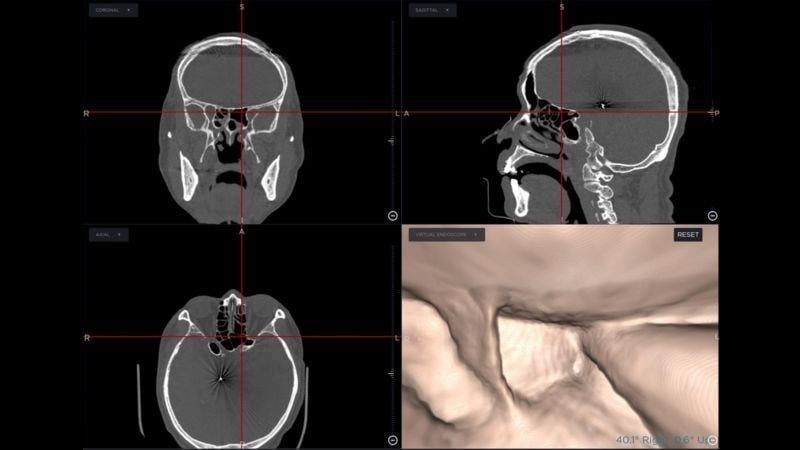

手術導航系統是利用患者的電腦斷層或核磁共振,製作出鼻竇附近的「google map」,此地圖中呈現出病人鼻竇細微的解剖結構、病灶、及周遭所有之神經、血管、腦部及眼窩的影像。隨手術進行中,依手術器械所在位置,可即時出現器械鄰近的解剖影像及結構,如同在地圖上即時呈現車子所在路況及周遭的建築物。使用此系統,在鼻竇的細微且複雜的結構中,開刀時就降低迷路的風險;器械可精準切除病灶,避免傷害鄰近的重要器官,對於患者與醫療團隊都是一大利器。

隨手術進行中,依手術器械所在位置,可即時出現器械鄰近的解剖影像及結構。